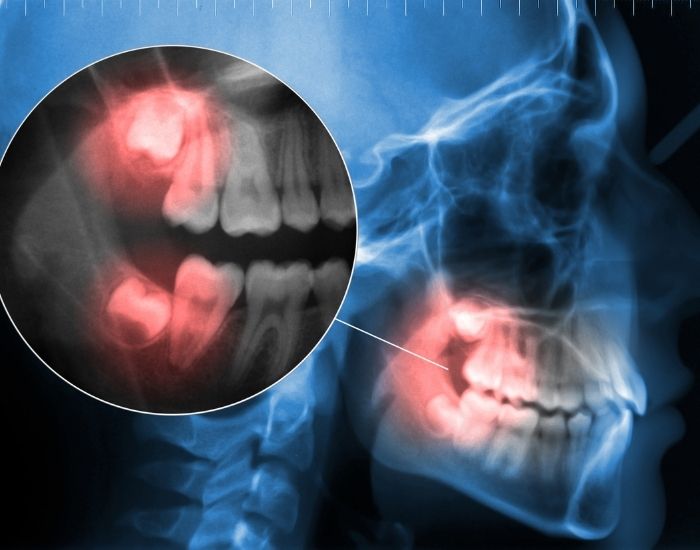

Digital X-rays

We use high-resolution digital imaging to see below the gumline. This helps us determine if your wisdom tooth is impacted, misaligned, or pushing against other teeth, which can lead to crowding and pain. -